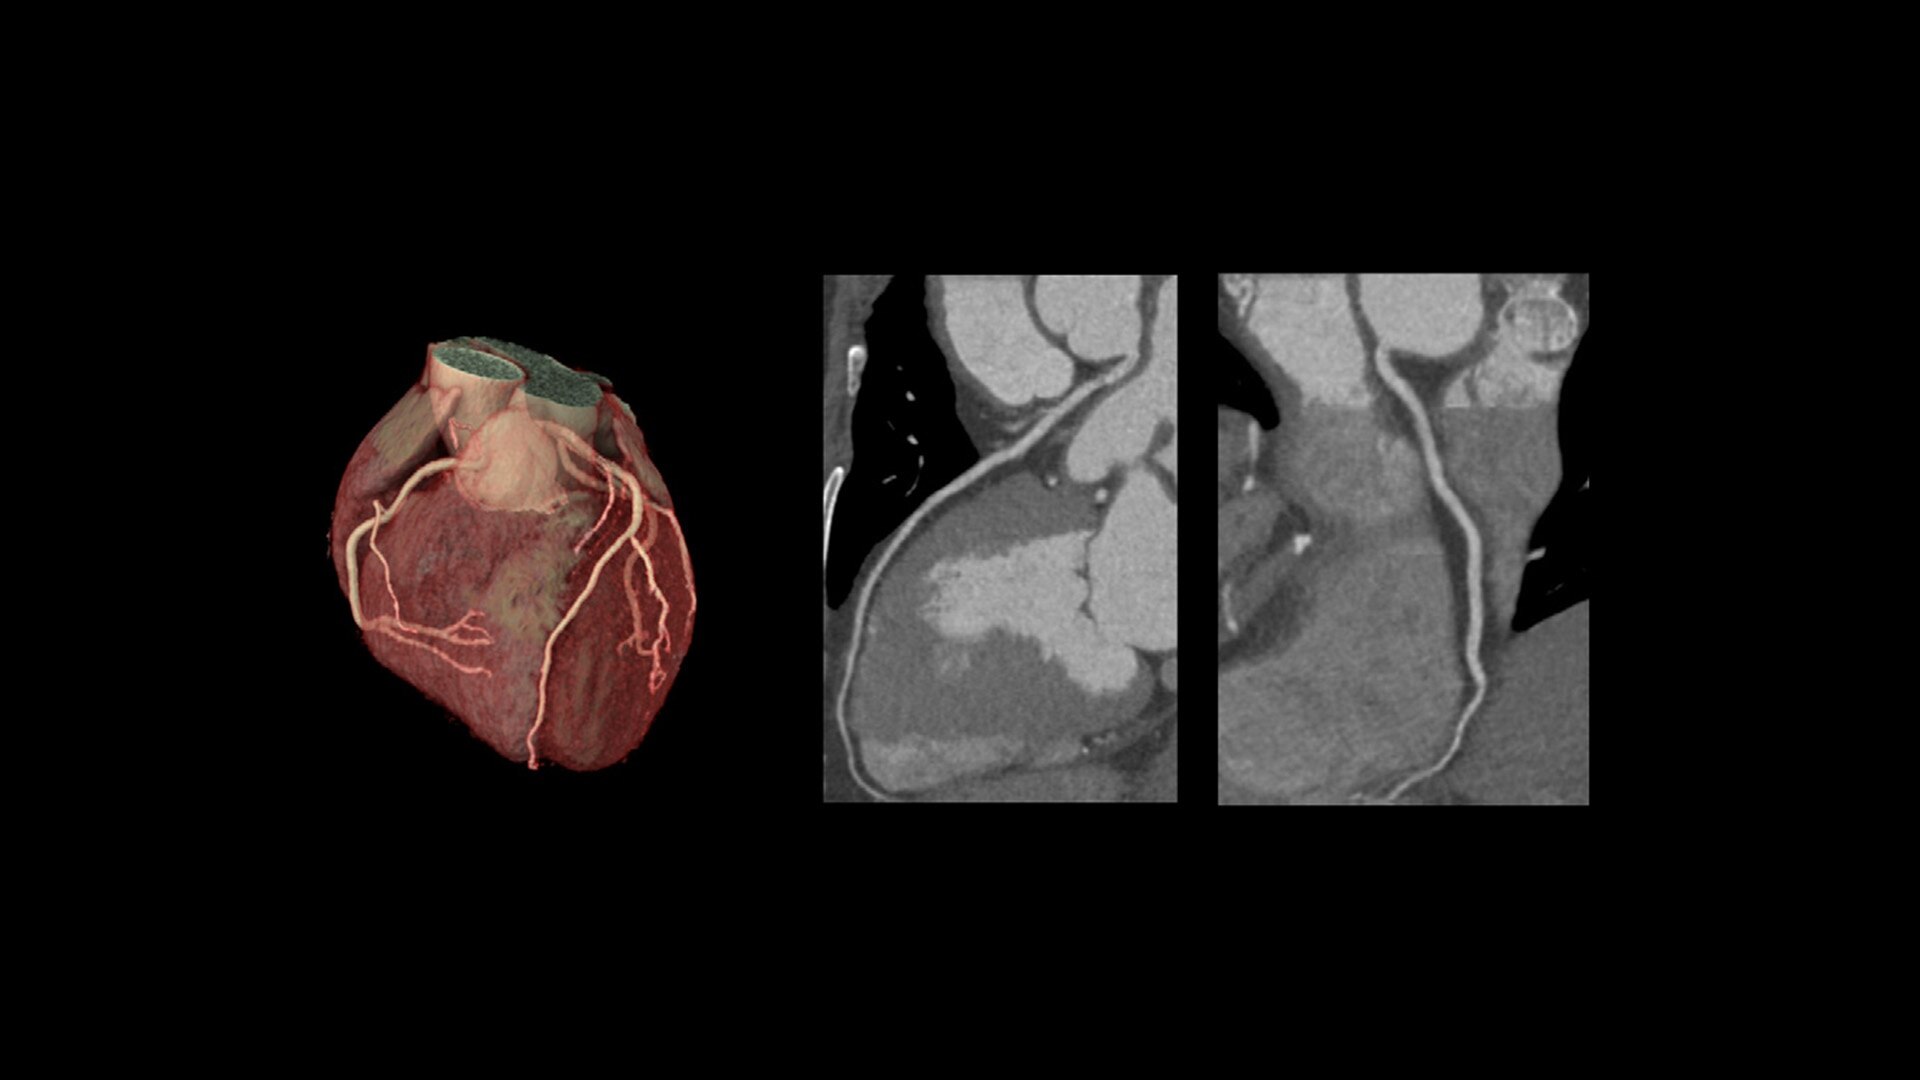

TrueFidelity DL + True Enhance DL

Better together

With the Revolution Ascend Platform, you can combine both of our AI-based imaging reconstruction technologies to create one stunning image. By combining True Enhance DL with TrueFidelity DL, you can achieve images that have less noise, enhanced sharpness and better noise texture than images obtained with ASiR-V.

True Enhance DL

Designed to enhance what matters

True Enhance DL is a deep learning-based processing method intended for contrast enhancement of single energy images. True Enhance DL uses a dedicated Deep Neural Network (DNN) trained to estimate monochromatic, 50 keV GSI images from single-energy X-ray. This technology brings four deep learning models that the user can choose depending on different contrast enhancement phases by clinical tasks.

TrueFidelity DL

Deep learning for a deeper understanding

TrueFidelity™ DL is our state-of-the-art image reconstruction technology that uses a DNN to generate high-definition, low-noise CT images. It produces images with exceptional sharpness, low-contrast image quality performance and your preferred noise texture, at the same dose.¹